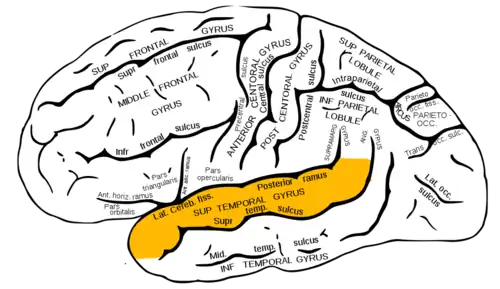

The study of the neuroanatomy of speech perception has been a topic of interest for over 130 years. [1] However, the full characterization of speech perception has yet to become complete. In the 1870s, Carl Wernicke [1] developed the first hypothesis in understanding the functional neuroanatomy of speech perception. Wernicke hypothesized that the auditory cortex supports speech perception from patients of his with auditory language comprehension disorders, typically with left superior temporal gyrus (STG) lesions (see Figure 1 for neuroanatomical location). Patients with these symptoms were later termed Wernicke aphasics. In the 1980s, Damasio & Damasio [2] found that large lesions to the left superior temporal gyrus did not lead to auditory speech comprehension problems, but rather deficits in speech production. These discrepancies in the literature created some ambiguity as to whether the STG was involved in speech perception or not. Damage to the left frontal, or inferior parietal areas created deficits in identification and discrimination of speech syllable tasks. [3] This discovery raises the question of the involvement of a frontal-parietal circuit in speech perception. The development of functional magnetic resonance imaging (fMRI), the ambiguity was not eliminated with the use of passive listening tasks as hoped. Activations were visible in all of these areas including the STG bilaterally [4]. Using syllable discriminations tasks Zatorre and collegues[5] found prominent activation in the left inferior frontal lobe. However, many authors have suggested that the inferior frontal lobe may have been activated as a result of task-dependent phonological working memory processes [6].

In the study of phonological processing, Steven Petersen and colleagues conducted a study on the cortical anatomy of single-word processing using positron emission tomography. They found key auditory processing areas to be bilateral activation of the primary auditory cortex, and temporoparietal cortex, anterior superior temporal cortex, and inferior anterior cingulated cortex, all left lateralized. They hypothesized the temporoparietal region near the angular and supramarginal gyri areas as a good candidate for the phonological coding region[9]. Then, in order to achieve proper lexical access the mapping of sound to a representation requires the integration of information on various time scales. In the study by Robert Zatorre and colleagues, they attempted to evaluate phonological processing in terms of these temporal, but also spectral changes in response to auditory stimuli. They found that there were distinct auditory cortex areas in each hemisphere, specific for each of these two parameters. The anterior auditory region in the right hemisphere showed greater cerebral blood flow to increasing spectral, rather then temporal, changes in stimuli. Whereas the same area on the left hemisphere showed the reverse pattern; a greater response to temporal changes in stimuli. The right superior temporal sulcus also showed increased response to spectral stimuli, but not to temporal parameters. Thus, the right auditory cortex appeared to respond less well to rapidly changing acoustic information characteristic of speech processing, where the left hemisphere was much better able to follow this stimuli [10]. Thus, as explained in Hickok 2010, a critical portion of the superior temporal sulcus is involved in phonological processes, particularly in the area bounded anteriorly by the anterolateral aspect of Heschl’s gyrus and posteriorly by the posterior end of the sylvian fissure[8].